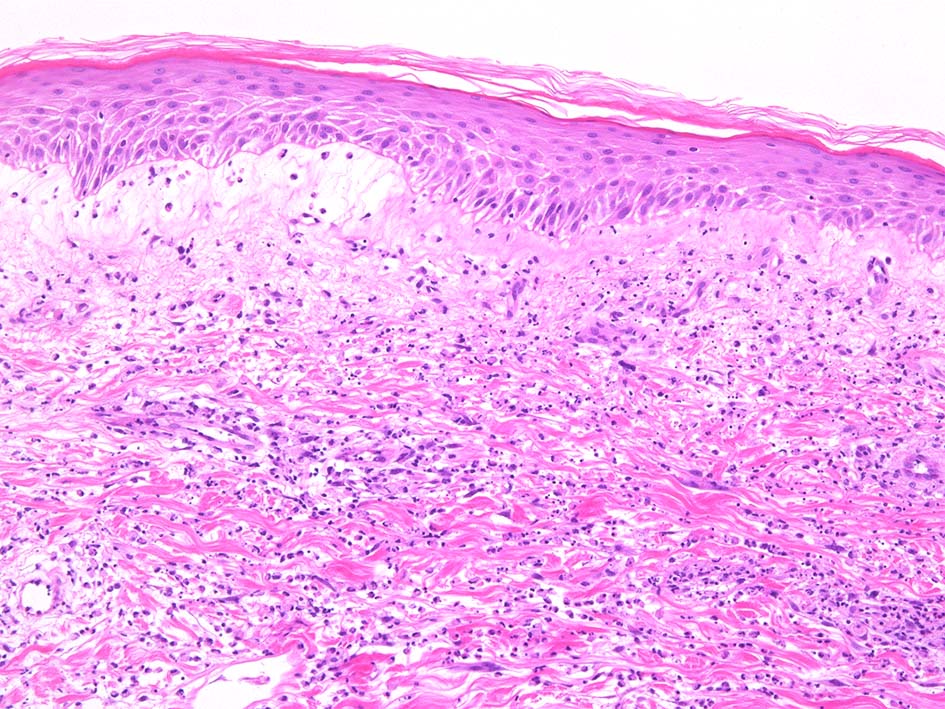

典型疹は真皮の好中球浸潤より始まる. 病初期では, 好中球浸潤は表皮に及ばない. 病期が進むにつれ, 2次的好中球浸潤が認められるようになる.

真皮上中層で広範囲に好中球が密に浸潤する所見がSweet病の最大の特徴. 好中球活性が亢進し, apoptosisを起こして核塵(核破砕物)がみられることが多い. 浸潤が顕著になると真皮上中層が浮腫をきたして, 皮疹が隆起する.

真皮上層浮腫がつよくなり表皮下水疱を形成することがある. 水疱内にはフィブリンや炎症細胞が多数認められる.

真皮の好中球浸潤部には毛細血管, 細動静脈が巻き込まれるが, 血管のフィブリノイド壊死は認められない.(鑑別が難しいことのあるBehçet病では2012年より, 壊死性血管炎があるとされており鑑別のための病理所見となっている)

HE x40. Sweet病最盛期皮膚病変の所見があります.

表皮下水疱, 真皮上層の細血管周囲に密な好中球浸潤あり.(thumb nail clickで大きなphotoが見られます)